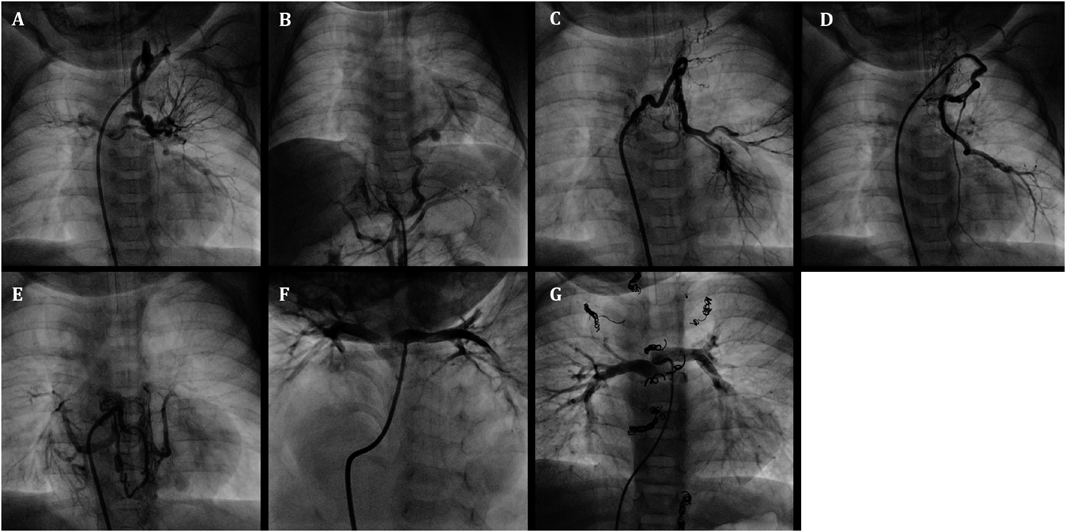

Fig. 2 Angiography of tetralogy of Fallot, subarterial ventricular septal defect, and pulmonary valve stenosis with major aortopulmonary collateral arteries (MAPCAs) in a 1-month-old boy

A–D: Frontal views of MAPCAs in selective angiography. E: Caudally angled left anterior oblique view of the native diminutive pulmonary artery (pulmonary artery index: PAI 49 mm2/m2) after the first balloon valvuoplasty. F: Final pulmonary artery (PA) in right ventriculography after transcatheter rehabilitation of the native PA at 16 months of age (PAI 229 mm2/m2)

An infant weighing 2610 g was delivered vaginally at 37 weeks’ gestation. He was transferred to our hospital on the day after birth for cyanosis and was diagnosed by echocardiography with tetralogy of Fallot, subarterial ventricular septal defect, pulmonary valve stenosis with a 39 mmHg pressure gradient involving a diminutive tethered pulmonary valve (diameter: 3.7 mm, z score: −5.5), and MAPCAs. He was also diagnosed with 22q11.2 deletion syndrome. His clinical condition was almost stable except for SaO2, which decreased from 85% to 65% at 1 month of age. The first cardiac catheterization revealed four MAPCAs originating from the subclavian artery and descending aorta (Fig. 2A–D), and a diminutive native PA (PAI 49 mm2/m2) (Fig. 2E). Each MAPCA had a sufficient dual supply with the native PA. In other words, the native PA was connected to the entire pulmonary vascular field. The first BVP was performed with full expansion of a 5.0 mm Sterling balloon (Boston Scientific, Natick, MA). Immediately after the balloon deflation, the patient’s SaO2 increased to 80%. The post-interventional course was uneventful, and the patient was discharged from the hospital. At 9 months of age, he received a second cardiac catheterization. The native PA had increased to a PAI of 147 mm2/m2, and a second BVP was performed to the pulmonary valve (diameter: 6.3 mm, z score: −4.0) with full expansion of a 7.0 mm Sterling balloon (Boston Scientific, Natick, MA) and 8.0 mm Tyshak II balloon (NuMED, Hopkinton, New York). The SaO2 rose from 80% to 88% and TAE of four MAPCAs was performed. After waiting for growth of the PA, a third cardiac catheterization was performed at 16 months of age. It revealed good pulmonary vascular condition with acceptable mean pulmonary artery pressure (11 mmHg) and pulmonary vascular resistance (1.1 U・m2). The native PA had grown to a PAI of 229 mm2/m2 (Fig. 2F) and the third BVP was performed on the pulmonary valve (diameter: 8.1 mm, z score: −2.7) with full expansion of a 9.0 mm Tyshak II balloon (NuMED, Hopkinton, New York). The patient’s SaO2 increased to 90% and TAE of the residual minor collateral arteries was performed. During this period, pulmonary valve regurgitation remained mild. At 21 months of age, he underwent a complete repair with a transannular patch. The postoperative course was uneventful, and echocardiography indicated acceptable right ventricular pressure; tricuspid regurgitation velocity was 2.8 m/s and inter-ventricular septum was round during systole in short axis view.